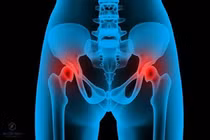

(khoahocdoisong.vn) - Để phẫu thuật thay khớp háng không chỉ căn cứ vào phim X-quang mà cần căn cứ vào triệu chứng (đặc biệt là triệu chứng đau), lứa tuổi và sau đó là điều kiện tài chính của bệnh nhân.

(khoahocdoisong.vn) - Người cao tuổi khi bị ngã không nên sợ phẫu thuật vì nằm thêm một ngày là bệnh thêm nặng. Việc thay khớp háng thành công sẽ giúp người cao tuổi bị té ngã có thể phục hồi sức khỏe và đi lại được.

(khoahocdoisong.vn) - Người già bị gãy cổ xương đùi (GCXĐ) chớ nên sợ phẫu thuật, nằm thêm một ngày là bệnh thêm nặng. Với công nghệ thay khớp háng bán phần và toàn phần người già, thậm trí trên 90 bị GCXĐ, vẫn có thể phục hồi sức khỏe và đi lại được.